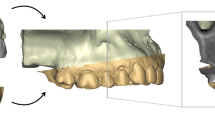

For the gold standard measurements, the adjacent intact teeth and part of the alveolar process were used as superimposition reference area (Fig. 1B). Perfect congruence of the two surface models is expected after a best-fit superimposition of the aforementioned identical surfaces, thus providing optimal spatial relation of the two gingival margins [15,16,17]. The test method measurements were obtained, by using the complete T1 or T2 clinical crowns as superimposition reference (Fig. 1C). An overview of the variables assessed in this study, with the corresponding abbreviations, is presented in Table 1.

The superimpositions were performed using the software’s iterative closest point algorithm (ICP) [19], following an initial manual approximation of the 3D objects to assist the automatic registration. Prior to any superimposition and measurement session, the position of the two models was reset to its initial state and the entire measurement process was repeated without reference to previous outcomes. The following superimposition settings were used for the GS measurements: 100% estimated overlap of meshes, matching point to plane, exact nearest neighbor search, exclude overhangs, 100% point sampling, 50 iterations. The CC measurement setting was the same as the GS setting, but with 30% estimated overlap of meshes, based on previous testing [16]. The ICP algorithm was iteratively applied until the distance between the two models was minimized.

Following each superimposition, the depth of the gingival recession was measured as described below. Firstly, a best-fit occlusal plane was defined by manually positioning landmarks on each tooth cusp or at the middle of the incisal edges of the anterior teeth. This step is required for initial automatic placement of the tooth long axis and the unadjusted preformed gingival margin curves by the software. The preformed curves were manually adjusted to each gingival margin (Fig. 2). Following the curve placement, the tooth long axis was definitely oriented by the operator considering all dimensions of space, through visual assessment of the original tooth model from different viewing angles. The axis passed through the center of each tooth that corresponds to the midpoint of the incisal edge for incisors, the center of the cusp for canines, the midpoint of the central groove for premolars, and the central pit for molars. An automated algorithm was afterwards implemented to vertically project each curve onto the user-defined tooth long axis. Along this axis, the most apical point corresponding to each curve was then automatically selected, and the distance between the two subsequent points was registered as the amount of gingival recession (Fig. 3). The orientation of the axis and the tooth center were reset and redefined before each measurement with the different superimposition techniques.

Gingival recession measurement. A Original model. B Recession model and superimposition reference area (blue). C Superimposed models and adjusted curves; colors appear slightly different because of the transparency of the original model. D Tooth long axis placement on the original model. E Overview of gingival margins and tooth axis. F Frontal and lateral view of the adjusted curves and tooth axis configuration; the deepest points of the curves are vertically projected onto the axis (blue lines) and the distance between their projections amounts to the gingival recession